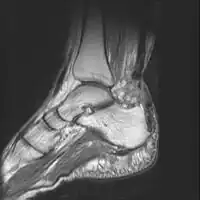

MRI can be used to discern incomplete ruptures from degeneration of the Achilles tendon, and MRI can also distinguish between paratenonitis, tendinosis, and bursitis. This technique uses a strong uniform magnetic field to align millions of protons running through the body. These protons are then bombarded with radio waves that knock some of them out of alignment. When these protons return they emit their own unique radio waves that can be analysed by a computer in 3D to create sharp cross sectional image of the area of interest. MRI can provide unparalleled contrast in soft tissue for an extremely high quality photograph making it easy for technicians to spot tears and other injuries.

Achilles tendon rupture -